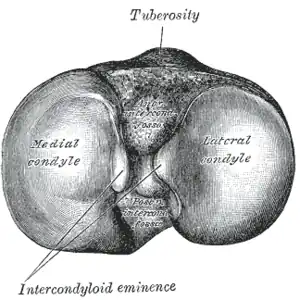

Sa face supérieure horizontale constitue le plateau tibial. Il est constitué de deux tubérosités formant les condyles du tibia : un latéral et un médial. Les deux sont recouverts de cartilage hyalin qui constituent les surfaces articulaires supérieures du tibia (la surface articulaire du condyle médial du tibia et la surface articulaire supérieure du condyle latéral du tibia). Elles sont séparées par la surface intercondylaire.

La tubérosité médiale est marquée en arrière par l'insertion du tendon direct du muscle semi-membraneux et en dedans par une gouttière de glissement pour le tendon réfléchi de ce muscle.

La tubérosité latérale porte en dehors et en arrière la facette articulaire fibulaire du tibia plane et arrondie. Elle regarde en bas, en arrière et en dehors et s'articule avec la fibula pour former l'articulation tibio-fibulaire proximale. En dehors et en avant se trouve le tubercule infra-condylaire (ou tubercule de Gerdy) qui donne insertion au tractus ilio-tibial.

Le condyle latéral est large et convexe vers le haut alors que le condyle médial est étroit et concave.

Entre les deux condyles la surface intercondylaire est constituée de trois parties :

- une moyenne constituant l'éminence intercondylaire constituée des tubercules médial et latéral intercondylaires,

- à l'avant de l'éminence se trouve l'aire intercondylaire antérieure du tibia,

- à l'arrière de l'éminence se trouve l'aire intercondylaire postérieure du tibia.

Les deux condyles s'articulent respectivement avec les condyles latéral et médial du fémur pour constituer l'articulation du genou.